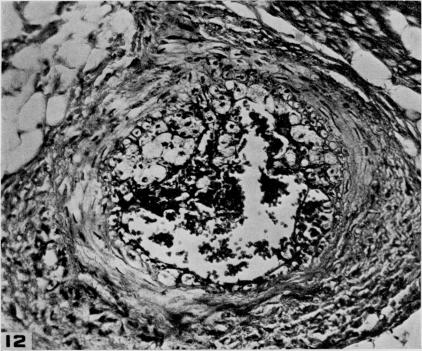

Studies on the pathogenesis of vascular disease; the effect of intravenous egg-yolk emulsions on inflammatory lesions of the aorta and coronary arteries of dogs.

Yale J Biol Med. 1956 Sep;29(1):9-22.